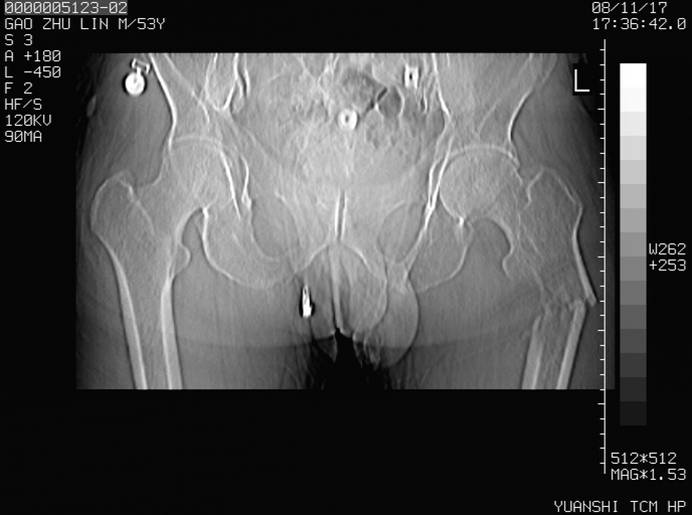

标题: CT16696:M53Y,左股骨上段骨折。 [打印本页]

标题: CT16696:M53Y,左股骨上段骨折。

左股骨上段外伤1个小时,左股骨上段疼痛。村医以腰椎间盘病变给以按摩及理疗数天。

图像不太清楚,左股骨上段外伤性骨折?病理性骨折?

建议上传骨窗!

左股骨上段粉碎性骨折;建议上传骨窗看看是不是病理性的啊!

左股骨上段粉碎性骨折,不排除病理性骨折可能。

考虑骨肉瘤伴病理骨折